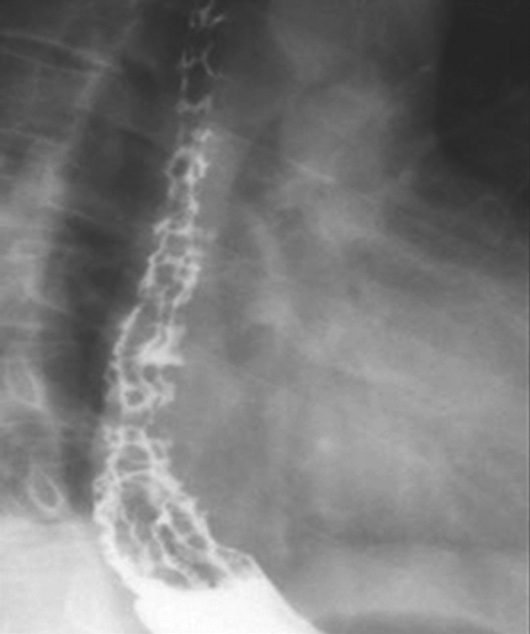

上消化道钡餐检查可见食管及胃底多发串珠状或蚯蚓状充盈缺损,食管腔轻度扩张,管壁蠕动减弱,病变常始于食管下段,后延及食管中段及胃底,极少数可波及食管上段。按静脉曲张的范围、程度及食管蠕动功能分为轻度、中度、重度。①轻度:静脉曲张最初局限性于食管下段,表现为黏膜皱襞稍增宽,可呈浅锯齿样表现。管腔可收缩排空。②中度:随着静脉曲张的发展,曲张范围超过下段累及中段。静脉增粗迂曲突向管腔,正常平行的黏膜皱襞消失,代之以纵行粗大结节样条状影,进一步表现为串珠状或蚯蚓状充盈缺损,食管边缘凹凸不平,由于黏膜下明显静脉曲张,食管腔被撑开而略显增宽,食管收缩欠佳,排空稍延迟。③重度(图5-21-34):后期静脉曲张扩展到中上段,甚至食管全长。严重的曲张静脉占据食管壁,并使肌层受压迫而退变,食管明显扩展,不易收缩,腔内见形态不一的圆形、环状或囊状充盈缺损,管壁蠕动明显减弱,排空延迟,但管壁仍柔软可扩张。

图5-21-34 重度食管静脉曲张钡剂检查结果

食管全长可见不规则蚯蚓状和结节状充盈缺损,食管明显扩展,蠕动明显减弱,排空延迟,管壁尚柔软